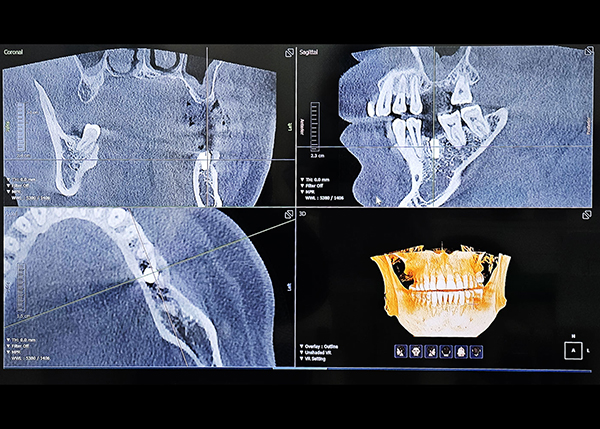

02

다양한 디지털 진단 장비보유

0.1mm 단위까지 오차줄인 진료

성공적인 임플란트 식립을 위해서는 정밀한 진단이 필수적입니다. 3D-CT, 구강 스캐너 등 다양한 디지털 장비를 이용하여 잇몸뼈, 치아, 신경 위치 등을 정확하게 진단해 오차를 최소화하고, 통증 및 출혈을 최소화해 더욱 안전하고 편안한 임플란트 식립이 가능합니다.

3D CT를 통한 컴퓨터 분석

현재 턱 뼈와 잇몸의 상태를 3차원 입체 영상으로 확인이 가능해

정밀 진단에 따른 오차 없는 수술이 가능